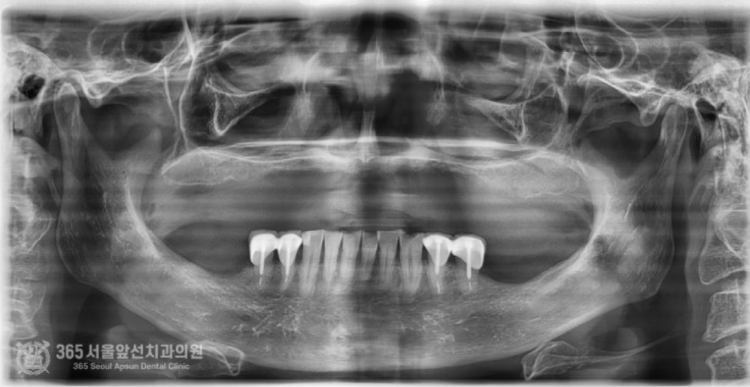

촬영일시: 2024.06.07. 처음 오셨을때 엑스레이 사진입니다. 윗턱과 아래턱 모두 뼈가 매우 적은편입니다. 특히 윗턱의 앞니쪽은 뼈가 고작 3mm밖에 존재하지 않았습니다. 매우 난증례에 해당한다고 볼 수 있겠습니다. 앞니 부위 뼈가 매우 부족하고(3mm) 어금니쪽도 전체적으로 뼈가 매우 적었습니다. 앞니와 어금니의 부족한 뼈를 만들어내면서 임플란트 식립을 계획했습니다. 통상적으로 윗턱에서 뼈가 부족할때 사용하는 수술방법으로 상악동거상술이라는 잘 알려진 술식이있는데요. 상기 환자분의 경우, 앞니쪽까지도 뼈가 부족했기에 코로 접근해서 부족한 뼈를 만들어 내는 비강거상술까지 동반하여 임플란트 수술을 진행했습니다. 촬영일시: 2024.08.10. 좌우측 상악동 거상과 비강거상을 동반하여 윗턱에 임플란트 8개를 식립했습니다. 지금까지 만나뵈었던 많은 환자분들 중 뼈의 상태가 매우 안좋은 편에 속하셨으며 매우 난해한 증례였습니다. 그렇지만 수술은 성공적으로 잘 마무리되었습니다. 위아래 전체 임플란트를 식립한 후 엑스레이 사진입니다. 임플란트가 가지런히 잘 배열되어있습니다 ㅎㅎ 지르코니아라는 재료를 사용하여 치아색상으로 단단하게 보철물도 제작했습니다. 촬영일시: 2024.12.29. 최종적으로 마무리된 엑스레이 사진입니다. 촬영일시: 2024.12.29. -노란색: 원래 환자분의 윗턱뼈 -주황색: 상악동거상술을 통해 만들어진 뼈 -보라색: 비강거상술을 통해 만들어진 뼈 최종적으로 치료가 완료된 후 구강내 사진입니다.